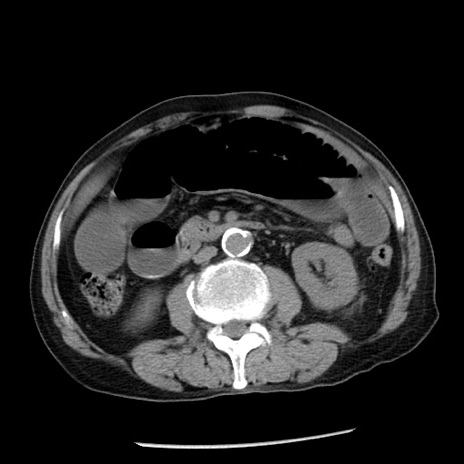

症例26(横断像)

【症例】80歳代男性

【主訴】嘔吐

【現病歴】昨晩2回嘔吐あり、今朝になっても嘔吐あり。来院。

【既往歴】胃潰瘍

【身体所見】意識清明、BT 37.6℃、BP 166/95mmHg、HR 100bpm、SpO2 97%、腹部:平坦・軟、腸蠕動音聴取良好、圧痛なし。

【データ】WBC 21900、CRP 1.46